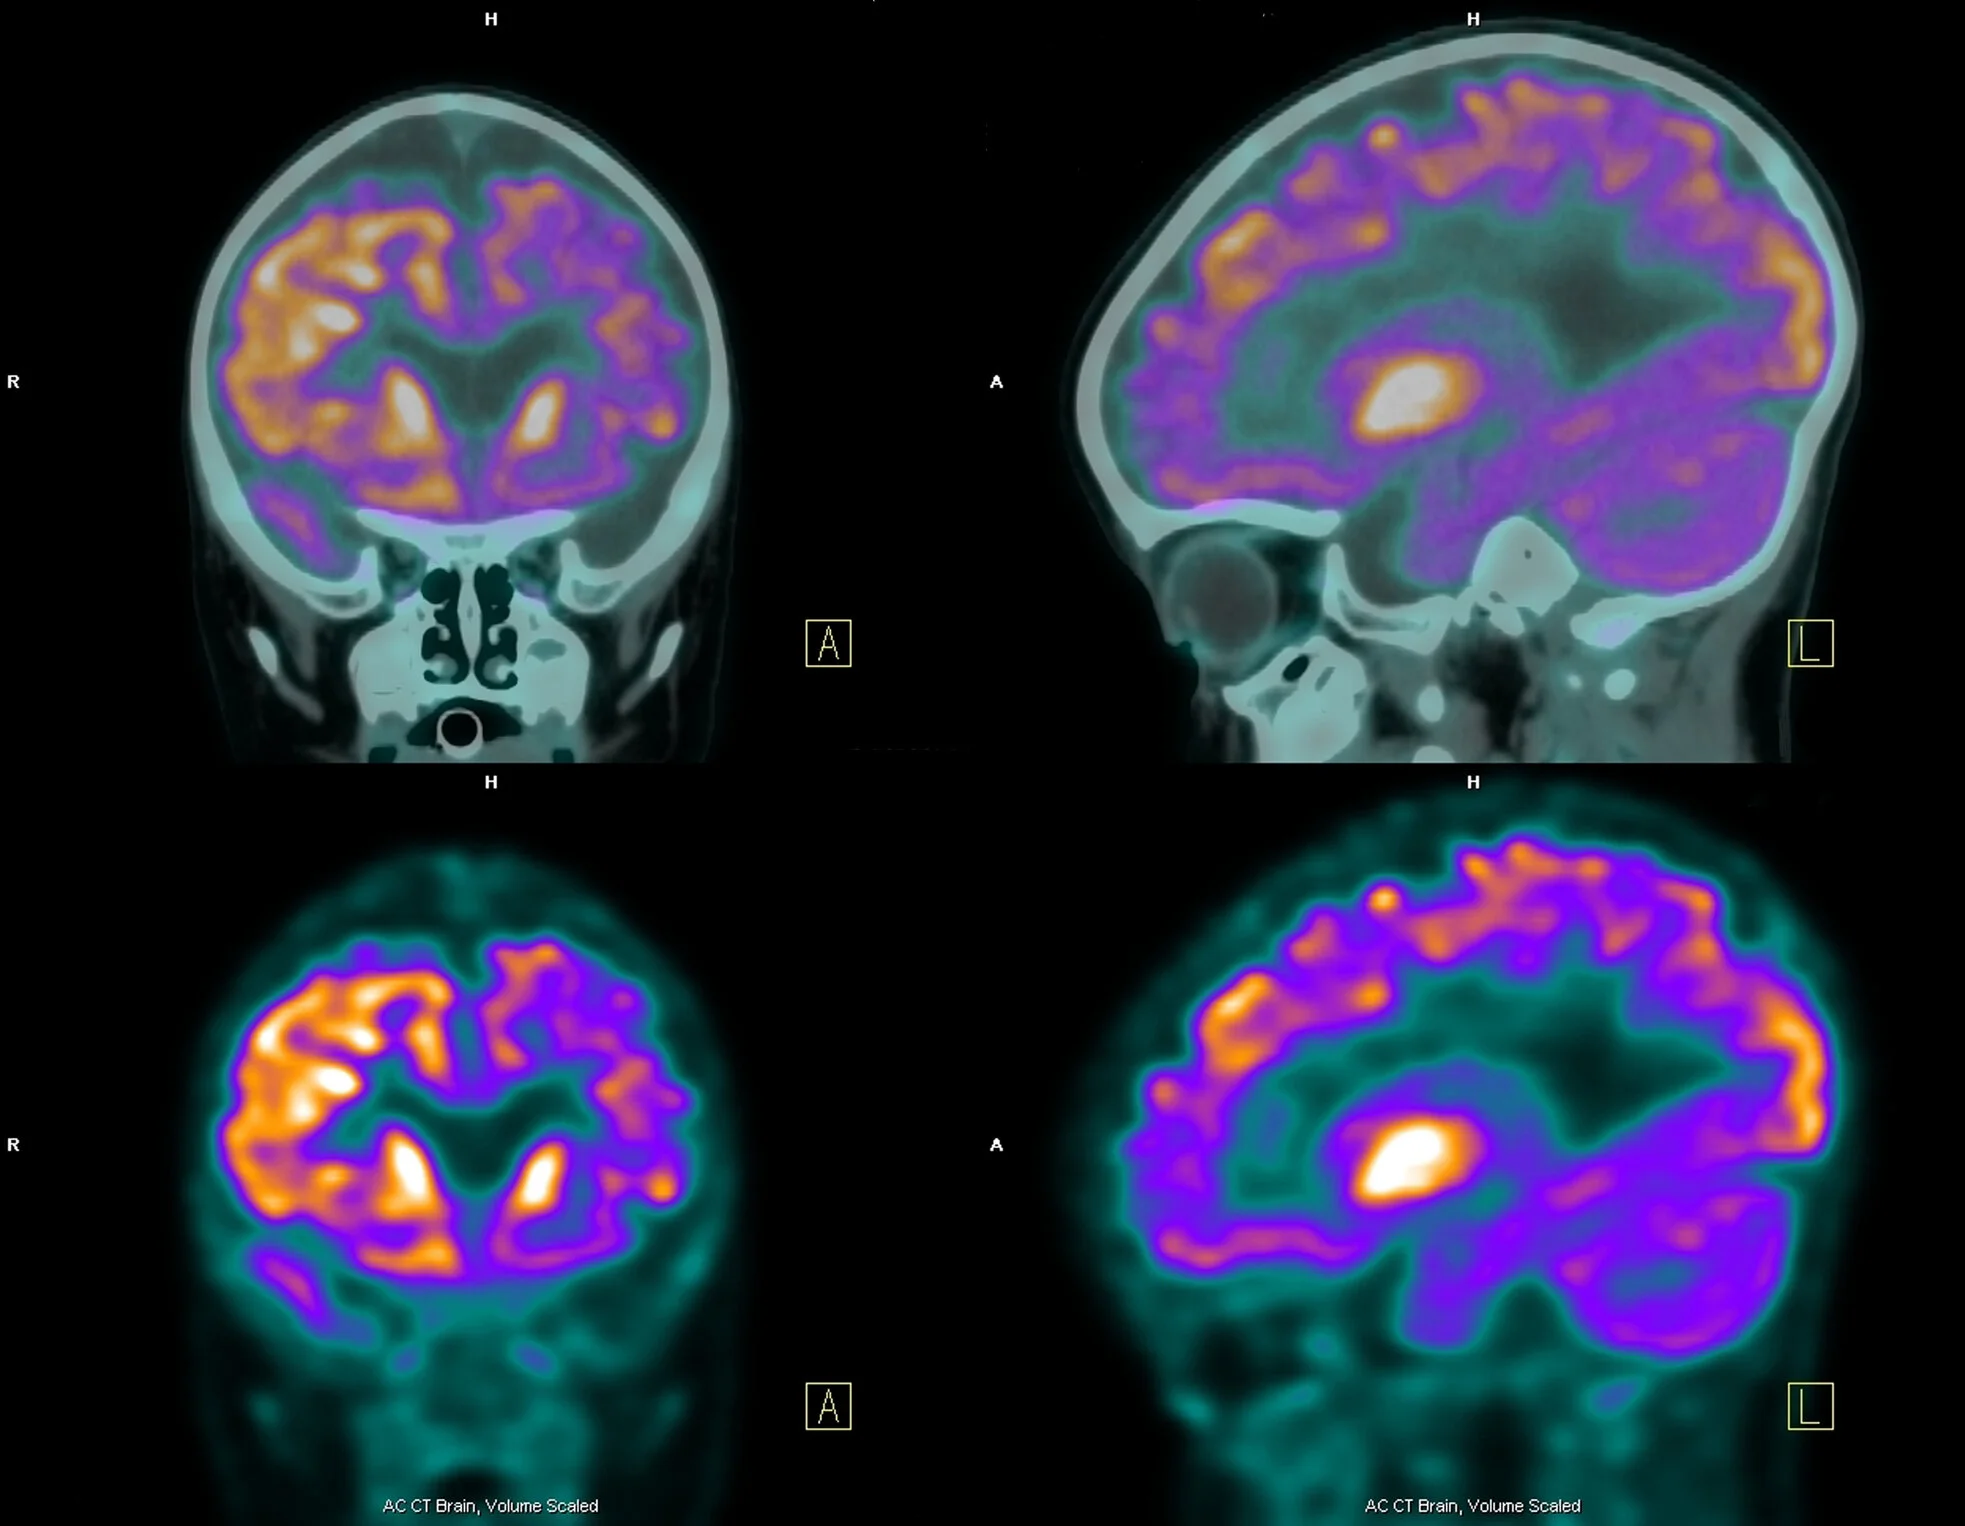

The biomarkers that Jack et al designate as demonstrating pathophysiology of neurodegeneration and neuronal injury are cerebrospinal fluid (CSF) total tau (t-tau), [18F]-fluorodeoxyglucose (FDG)-PET hypometabolism, and atrophy on structural MRI in the regions characteristically affected in AD. Having both CSF biomarkers and imaging as part of the classification gives both an absolute value to demonstrate abnormality but also an image to show the extent of the affects throughout the brain. AD often shows an increase in t-tau, but more significantly CSF t-tau is shown to increase in traumatic brain injury and stroke and correlates with the severity of damage. This indicates that CSF t-tau levels can reflect the severity of neuronal degeneration at a specific point in a person’s AD progression. [18F]-(FDG)-PET hypometabolism is used to measure the rate of glucose metabolism. The brain metabolizes glucose to function, therefore we can demonstrate brain damage if areas of the brain are not metabolizing glucose. Finally, atrophy is very characteristic of AD with cortical thinning, enlarged ventricles, and loss of hippocampal volume often seen due to neurodegeneration and loss of synaptic connections and neuronal branching. Although, both atrophy and hypometabolism are not specific to AD, they are found to behave similarly to CSF t-tau when compared to clinical symptoms. These biomarkers also allow clinical trials to study more treatment related outcomes. Historically, cognitive tests were the sole outcome compared longitudinally while the patient was alive, but these are often not objective. The ability to quantitatively demonstrate disease progression, stagnation, or improvement over time has been revolutionary in demonstrating treatment efficacy, or lack thereof.